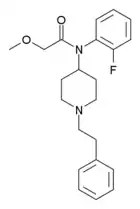

Anilidopiperidines